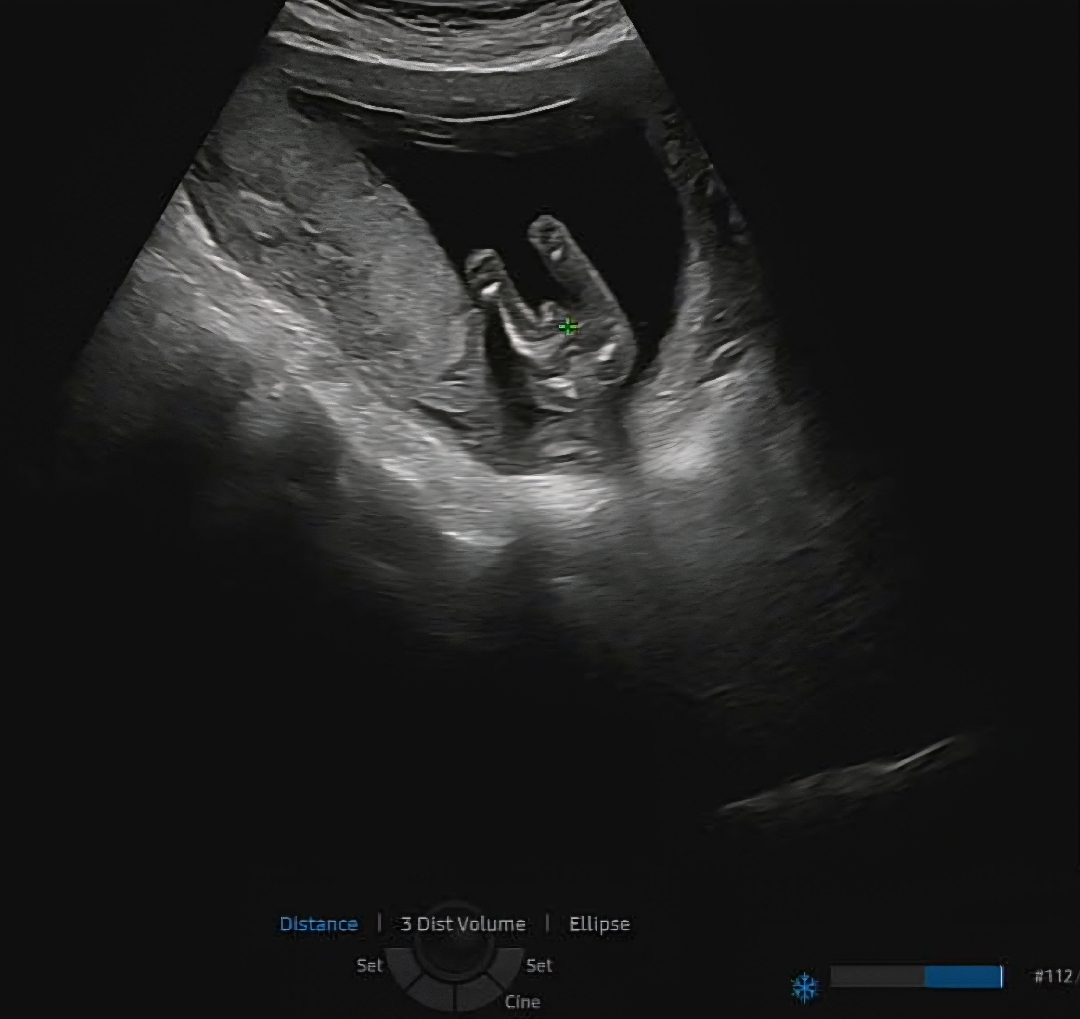

14주4일엔 매끈하니 딸 일것같다 근데 아직 이르니 다시 확인해보자 하시고 너무 빨리 지나가서 제대로 못보고 15주2일 다른 병원에서 갑자기 화면 뽝 틀어주시면서 고추가 보인다며 아들이네요? 하더라구요....대체 뭘까요 ㅠㅠ 사진 확신의 아들 고추 맞나용?!?!?!

빼박 아들입니다 ㅇ_ㅇ/ 축하드려용 왕자님!

딸에서 아들로 성별반전은 꽤있다하더라구용 아들같아여..!

아들인거같아요~!

제가 봤을때두 아들같아용..ㅠㅠ